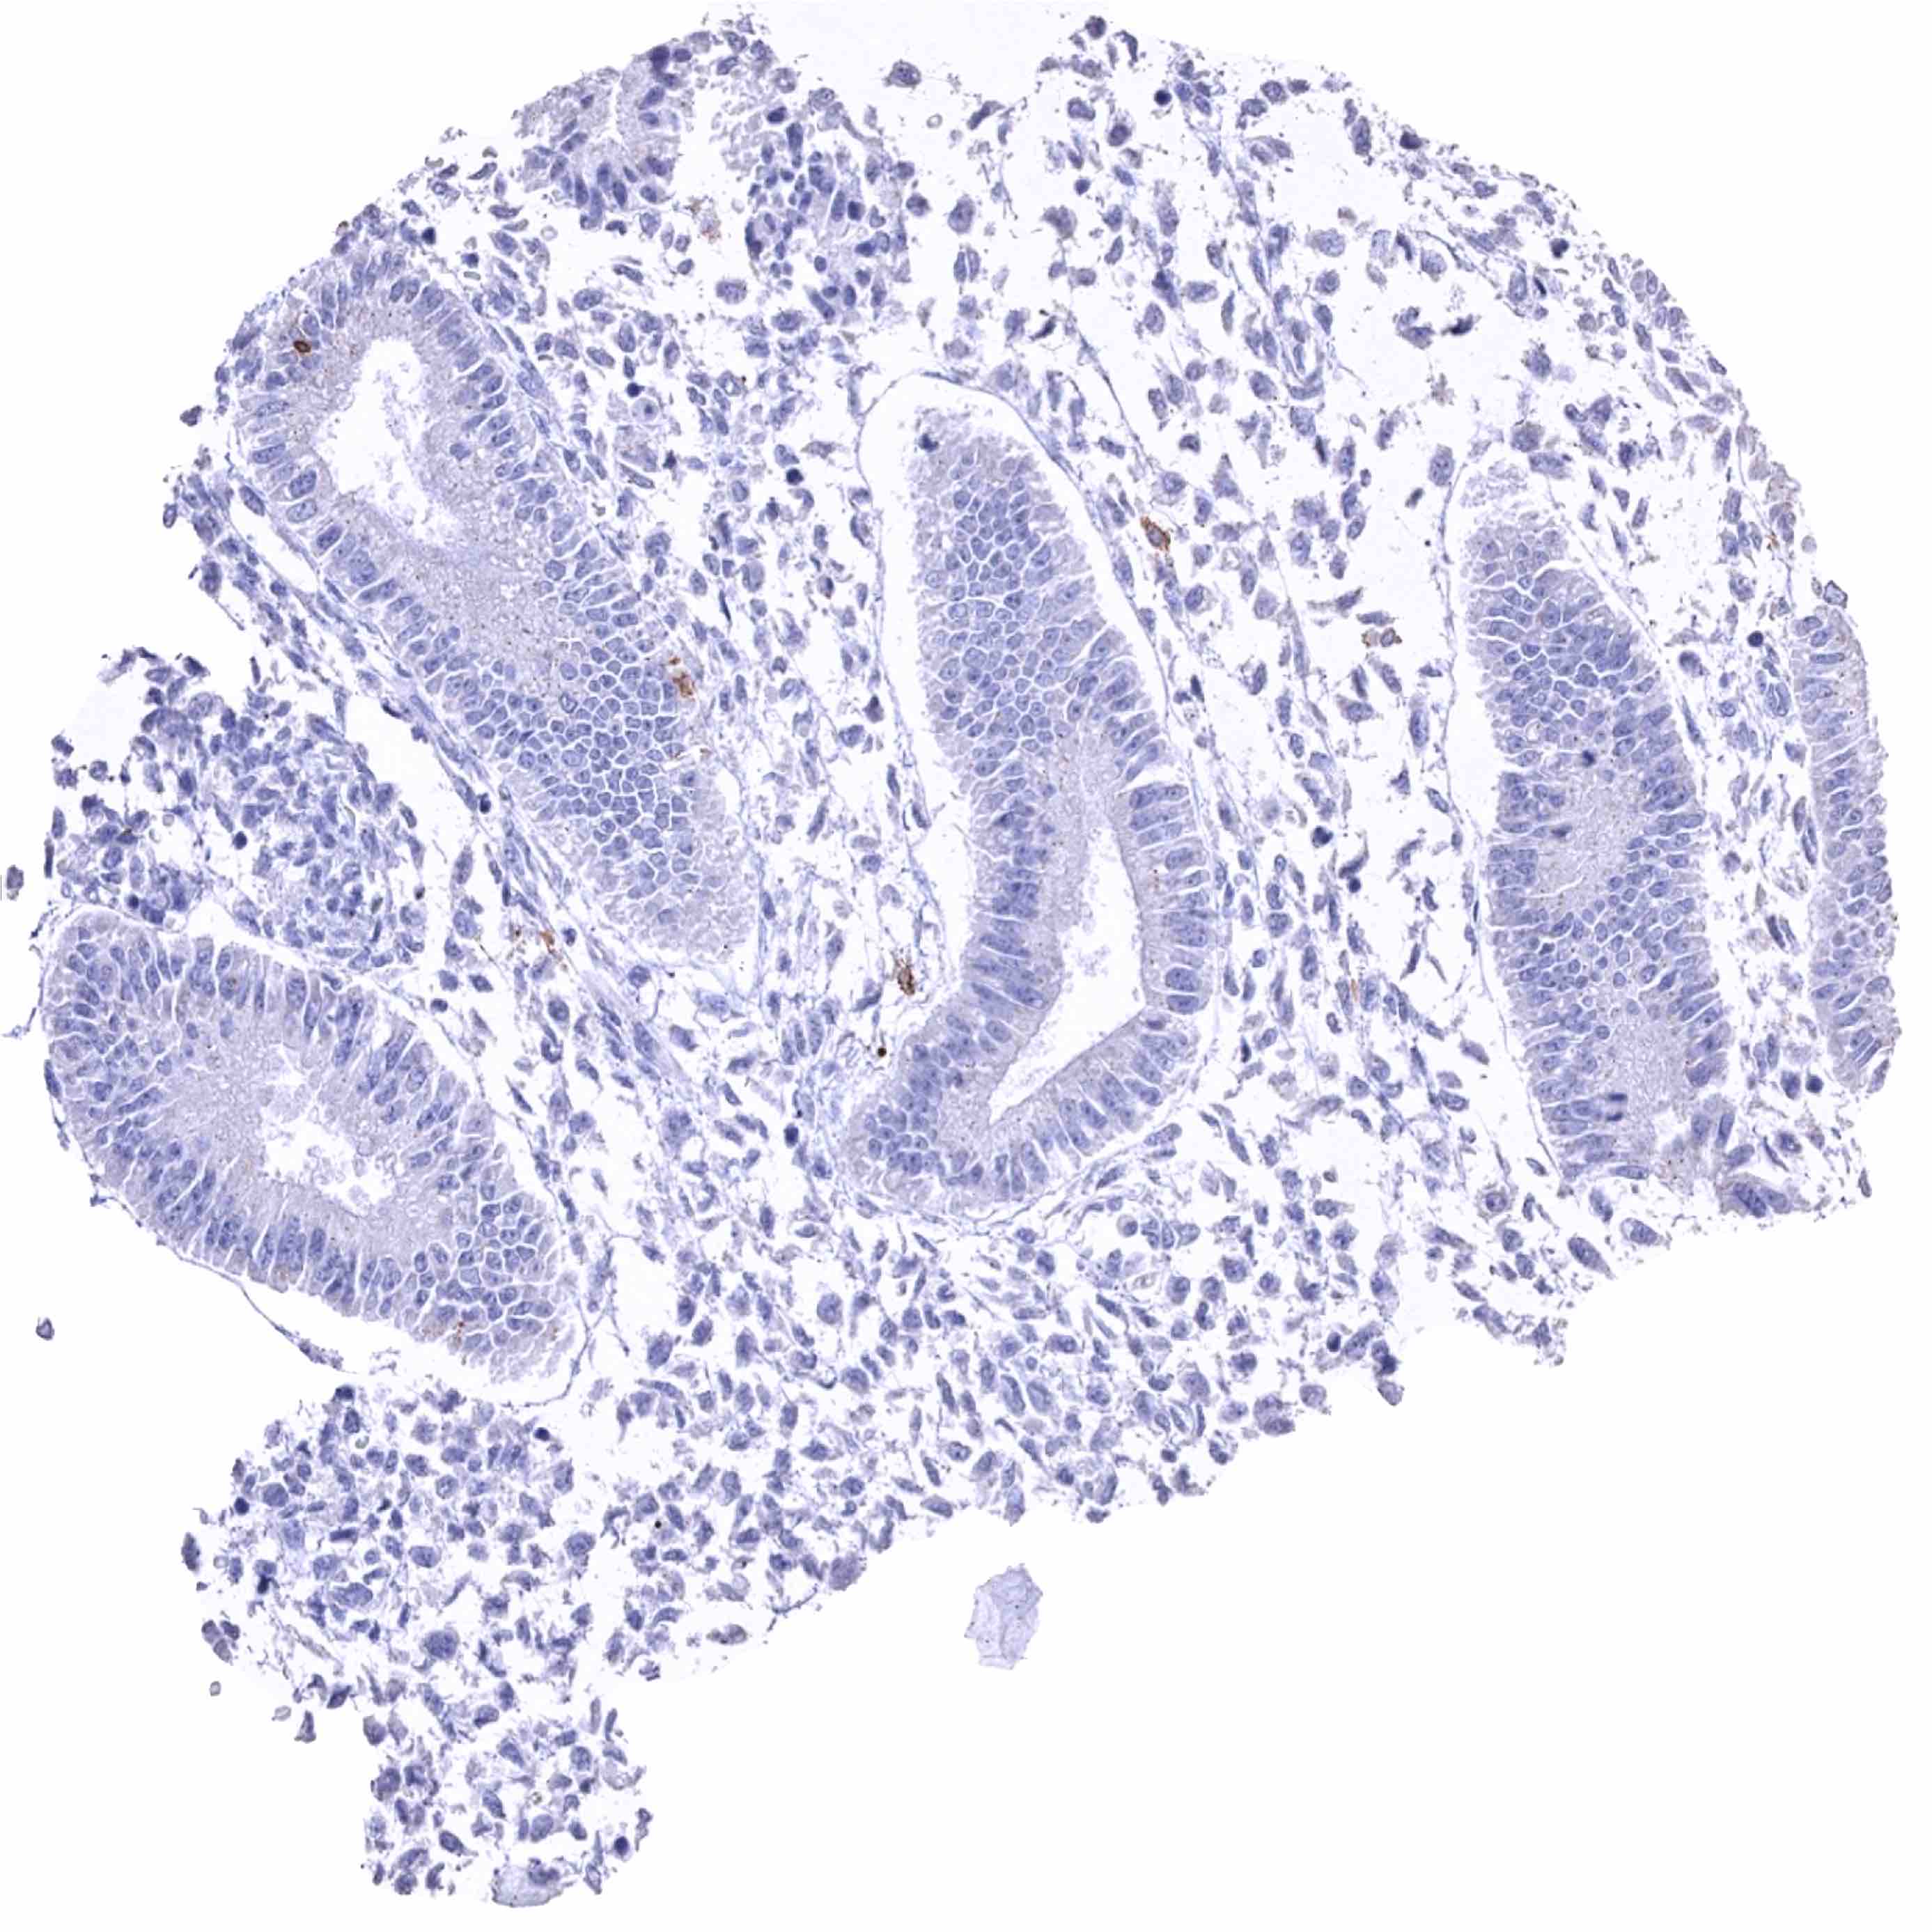

Duodenum, mucosa – Strong CD38B staining of numerous inflammatory cells